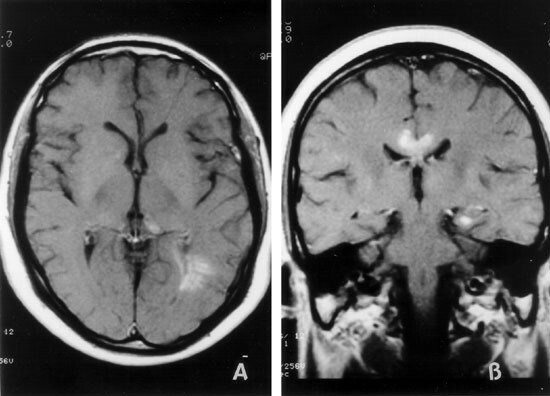

• Tercer periodo de la neurocirugia (imagen diagnostica)

Tercer periodo de la neurocirugia (imagen diagnostica)

• Houndsfield y Cormack

Houndsfield y Cormack

La Tomografía Axial Computarizada (TAC) hizo que ellos fueran merecedores del Premio Nobel al permitir por primera vez, la visualización de lesiones a partir de imágenes del interior del cráneo.